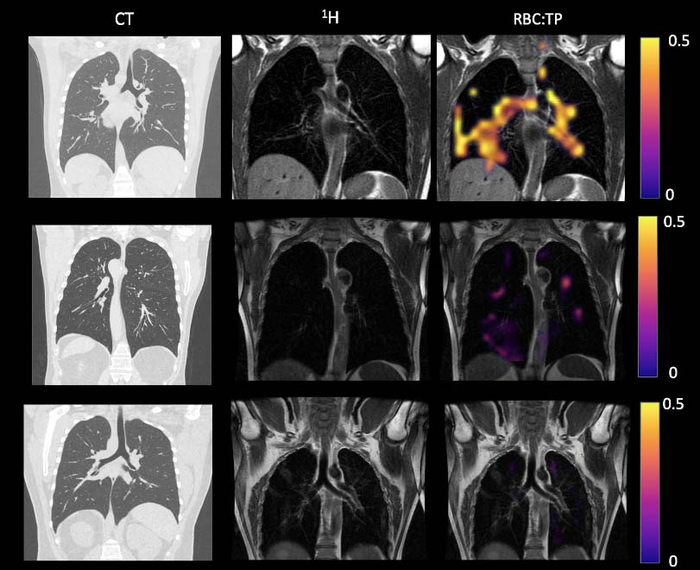

OAK BROOK, Ill. – A special type of MRI found lung abnormalities in patients who had previously had COVID-19, even those who had not been hospitalized with the illness, according to a new study published in the journal Radiology .

“In a collaboration between the University of Oxford and the University of Sheffield, we have been able to identify abnormalities in the lungs of both hospitalized and non-hospitalized participants using a novel imaging technique, Hyperpolarized Xenon 129MRI, or Hp-XeMRI,” said the study’s senior author, Fergus Gleeson, M.B.B.S., from the Department of Oncology, University of Oxford and Department of Radiology, Oxford University Hospitals NHS Trust. “These abnormalities are not apparent on conventional imaging, and in some individuals were detected up to a year after their initial COVID-19 infection.”

Hp-XeMRI has shown promise in detecting abnormalities of alveolar gas exchange—where oxygen moves from the lungs to the bloodstream and carbon dioxide passes from the blood to the lungs—even when CT scans and lung function tests were normal. Hp-XeMRI enables the assessment of ventilation and gas exchange into red blood cells. It provides regional information of pulmonary vasculature integrity and may be able to identify lung abnormalities not apparent on CT.

“We saw that the ability of gas to transfer from the lungs into the blood stream was less in non-hospitalized patients in comparison to those hospitalized with COVID,” Dr. Gleeson said. “Furthermore, both groups of participants had lower dissolved phase Hp-XeMRI values than healthy participants, pointing to potential defects in either the lining of the lung or the surrounding blood vessels.”

The results showed that there were significant differences in mean red blood cell to tissue plasma ratio between healthy controls and PHC/NHLC participants, indicating potential differences in lung function.